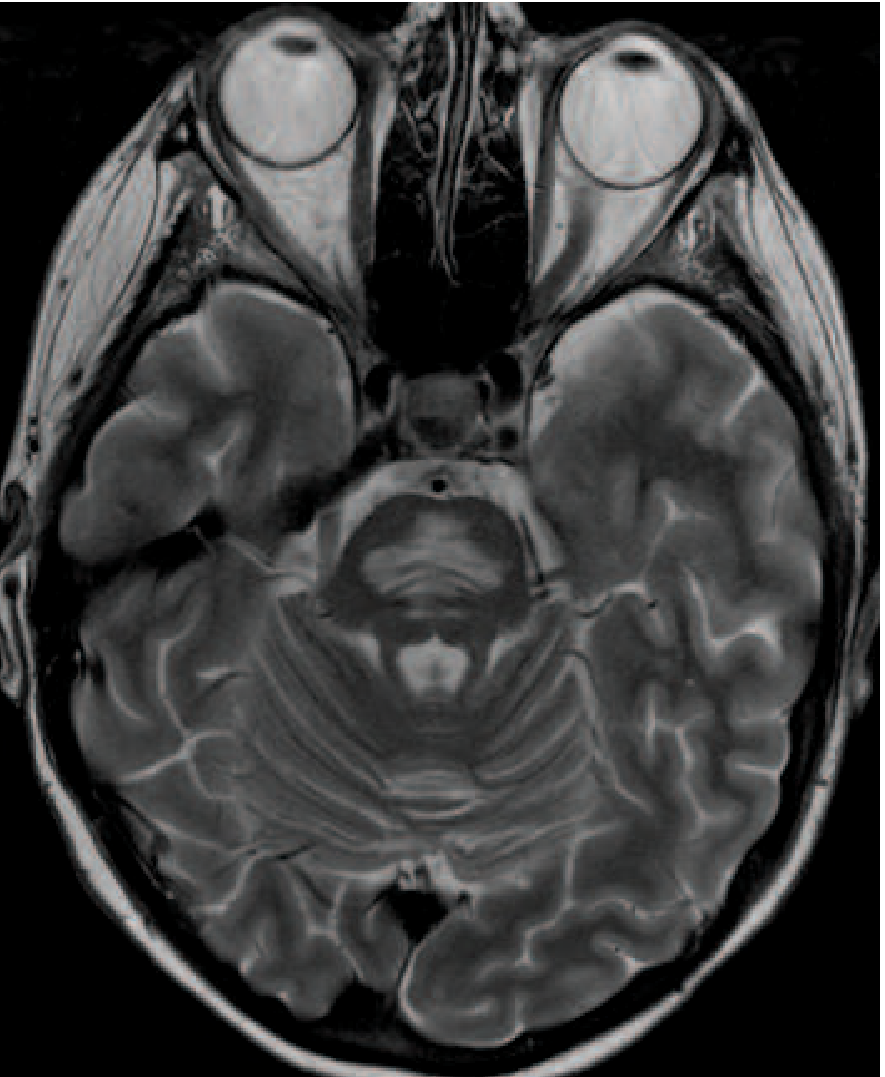

MRI (Harrison's 22E) — axial T2 through the pons showing symmetric pontine hyperintensity:

Osmotic demyelination syndrome — axial T2 MRI showing symmetric pontine high signal involving transverse pontine fibers with sparing of corticospinal tracts

Axial T2 MRI showing symmetric pontine hyperintensity in ODS, with characteristic sparing of corticospinal tracts. — Harrison's Principles of Internal Medicine 22E, Fig. 318-5

• T2-weighted / FLAIR: Symmetric hyperintensity in the central pons, characteristically involving transverse pontine fibers while sparing the descending corticospinal tracts (gives a "trident" shape)

• Diffusion restriction may appear in the lower pons within a day or so of motor signs; T2 changes typically appear several days later